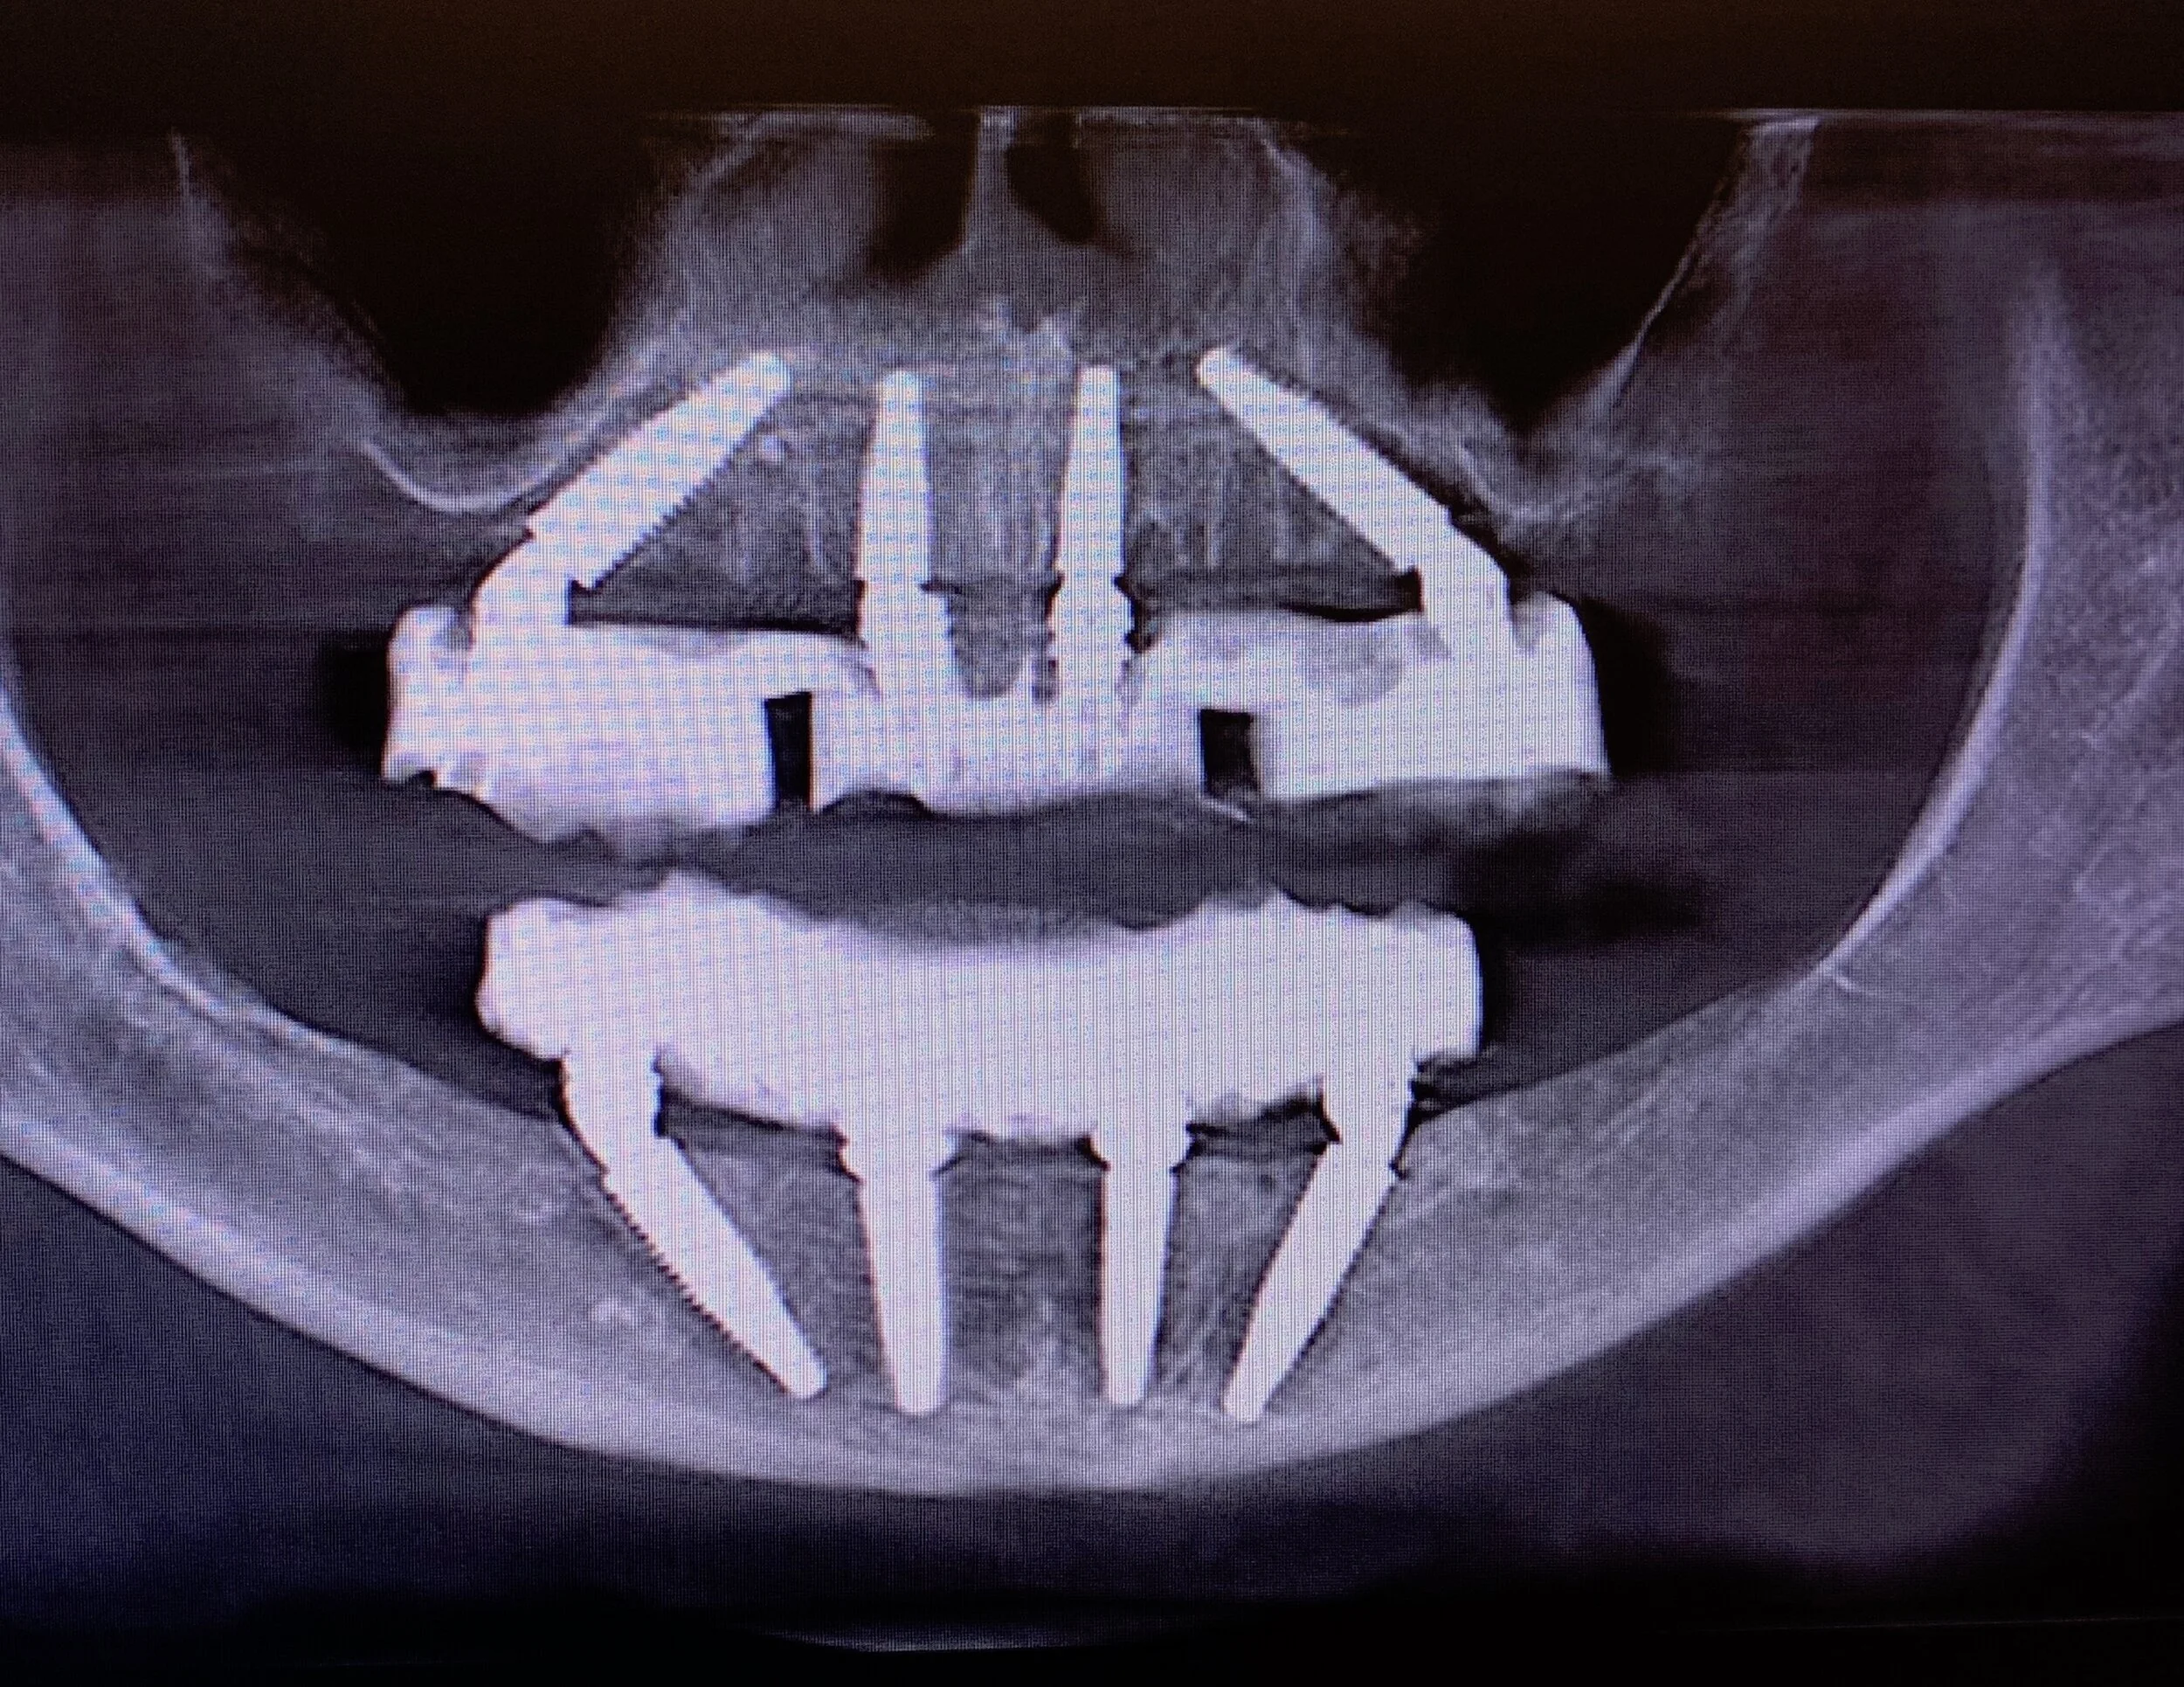

All on X Standard Cadaver April 11-12, 2025

Join Dr. Clark Damon in Dallas TX for All on X Standard Full Arch Implant education on Cadavers. April 11-12, 2025.

Join Dr. Clark Damon in Dallas TX for All on X Standard Full Arch Implant education on Cadavers. April 11-12, 2025.

Join Dr. Clark Damon in Dallas TX for All on X Standard Full Arch Implant education on Cadavers. April 11-12, 2025.